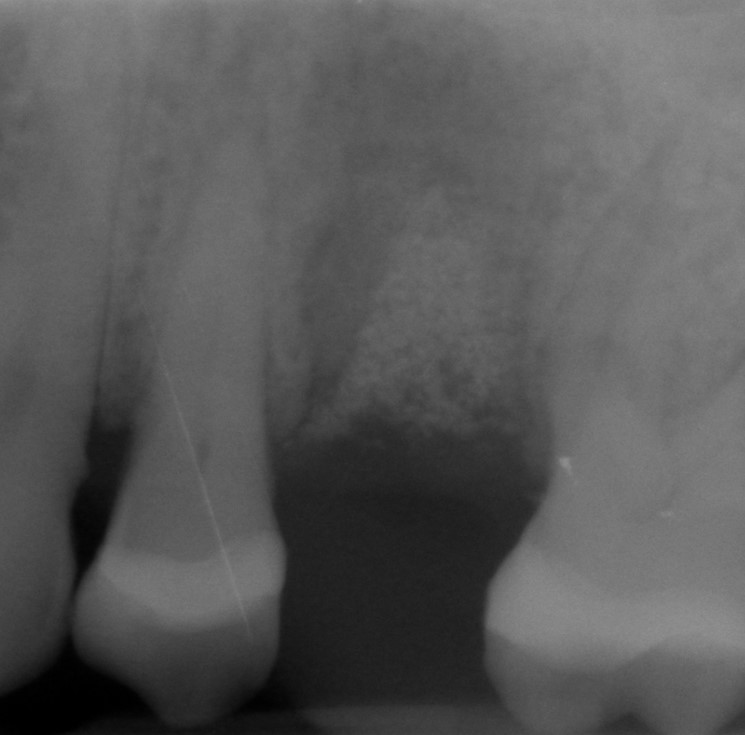

Intrabony defect treated using collprotect® membrane & cerabone® (1) - Cosgarea & Sculean

Pre-surgical probing reveals a deep intrabony defect on the distal aspect of the upper canine.